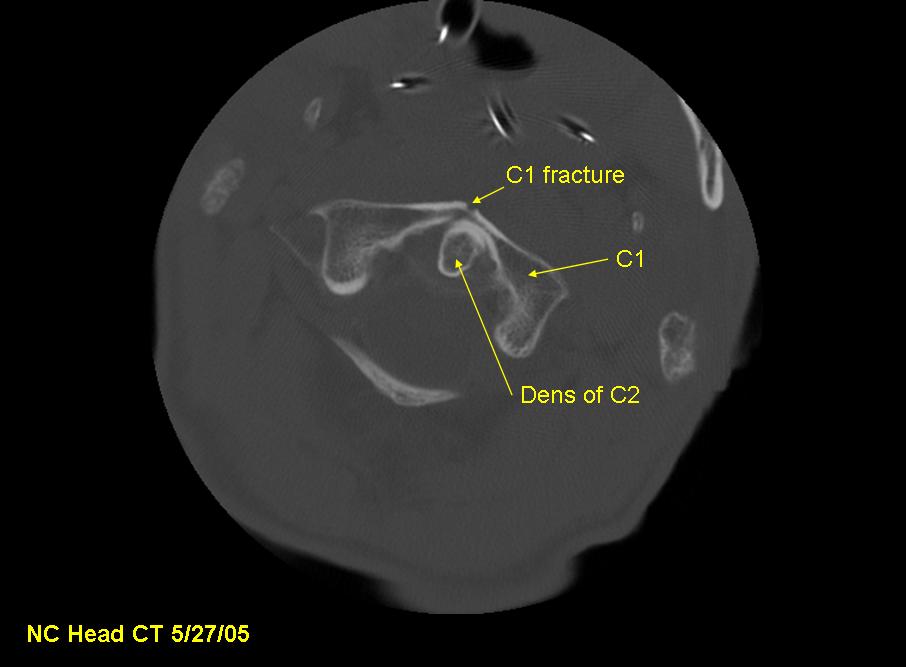

X-ray, CT, and MRI image studies at the hospital show C1 and C2 fractures with spinal cord injury, resulting in quadriplegia. T2-T4 spinous processes and several left ribs are also fractured. The patient never regains consciousness and dies the next day.

The dens, also called the odontoid process, is the portion of the C2 (the "axis") about which the C1 and the head rotate. Because the dens extends superiorly into the ring of C1, it is subjected to shear forces and fracture from C1 in neck injuries. The dens can then impact the spinal cord, injuring or severing it. In this case, although the patient's spinal cord was not severed, impact from the dens caused a spinal cord hematoma resulting in quadriplegia.